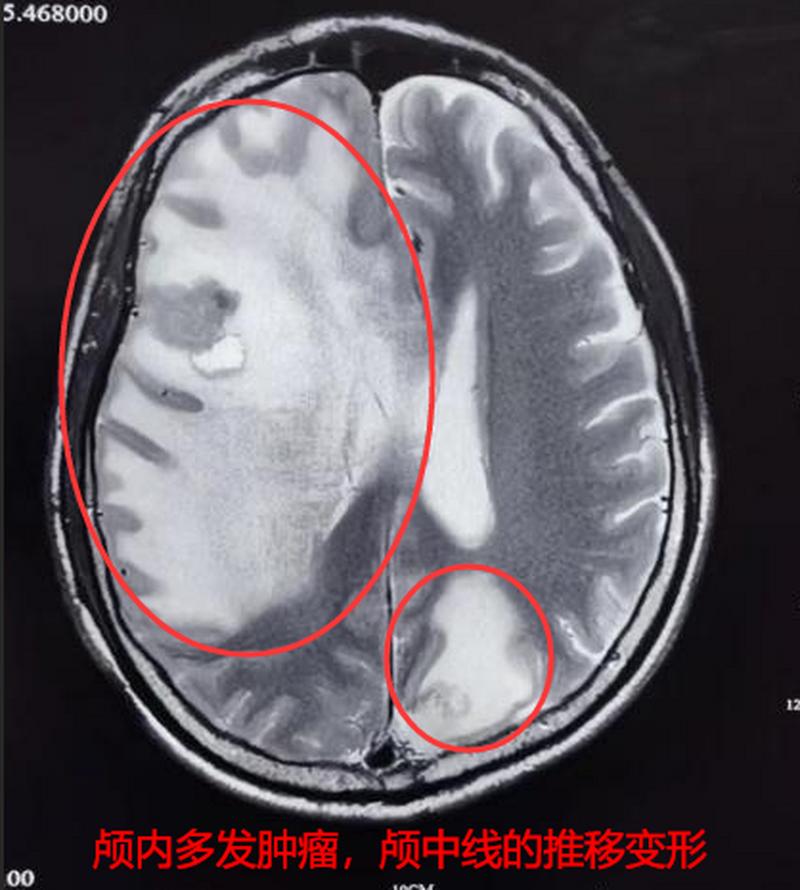

- 本质:这是癌细胞从肺部通过血液循环转移到了大脑,形成了新的肿瘤(转移灶),这是癌症的晚期表现,意味着癌细胞已经扩散到全身。

- 占位效应:脑瘤会像“占道施工”一样,挤压周围的正常脑组织,导致颅内压增高,引起头痛、呕吐、视力模糊等症状。

- 神经功能损伤:根据脑瘤位置不同,会破坏控制运动、语言、感觉等功能的神经通路,导致偏瘫、失语、癫痫等。

- 癌症进展:如果不加控制,脑瘤会继续生长,导致病情迅速恶化。